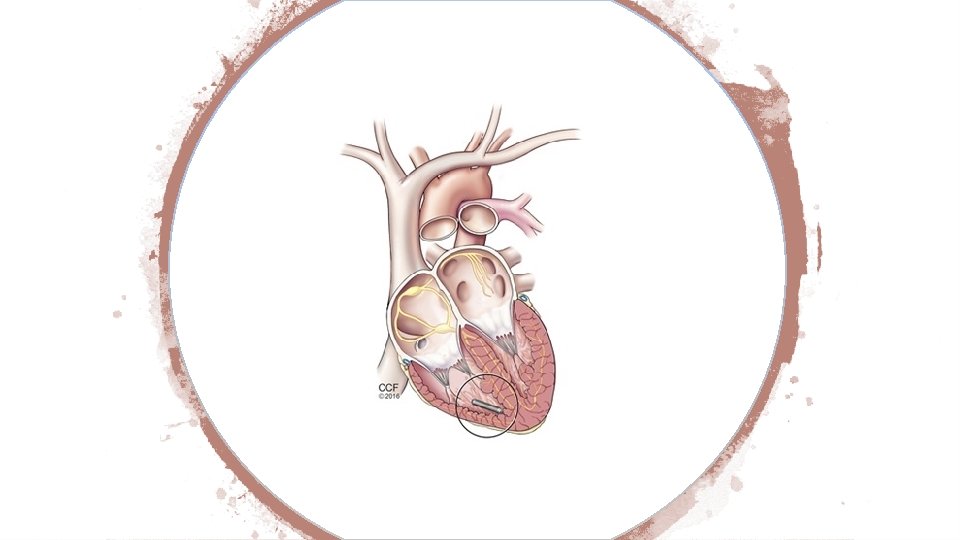

Pacemaker Changes Category III codes 0387 T-0391 T were deleted and replaced with permanent codes 33274 (Transcatheter insertion or replacement of permanent leadless pacemaker, right ventricular, including imaging guidance [eg, fluoroscopy, venous ultrasound, ventriculography, femoral venography] and device evaluation [eg, interrogation or programming], when performed) and 33275 (Transcatheter removal of permanent leadless pacemaker, right ventricular).

New guidelines state that insertion of a catheter into the right ventricle is included in the insertion, replacement or removal of a leadless pacemaker system. In addition, right heart catheterization codes 93451, 93453, 93456, 93457, 93460, 93461 and 93530 -93533 should not be reported with the insertion or removal codes unless the right heart catheterization treats a condition that is “distinct from the leadless pacemaker procedure. ” And when a system is removed and replaced during the same session, report 33274.

Aortic Procedure 33440 Replacement, aortic valve by translocation of autologous pulmonary valve and transventricular aortic annulus enlargement of the left ventricular outflow tract with valved conduit replacement of pulmonary valve (Ross-Konno Procedure)

In layman's terms it means that they will take out his diseased aortic valve and replace with his own pulmonary valve